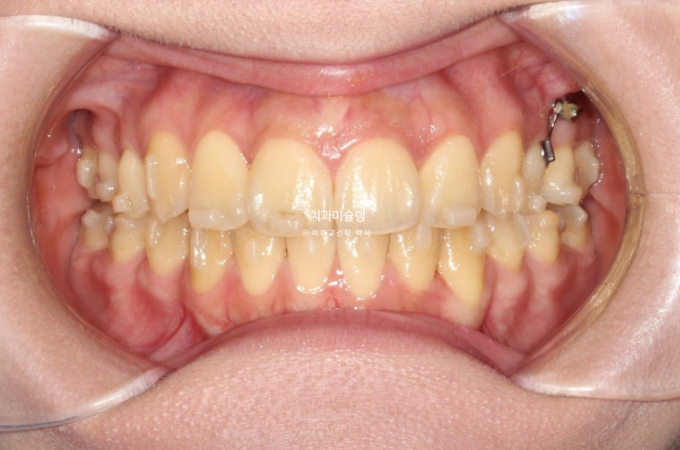

중심선과 앞니 높낮이는 완벽합니다.

26.01

중심선은 일치하고

어금니 교합은 물샐틈 없는 1급 교합관계를 보이며 쫀쫀하죠 (?)

개방교합이 해소되어 잘 물립니다

중심선 불일치는 해결이 되었습니다.

교합이 좋습니다.